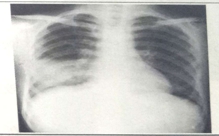

临床执业医师实践技能考试模拟题——影像学(6分)

第一站X线检查模拟试题——临床执业医师实践技能

临床执业实践技能模拟习题:X线-心脏增大(二尖瓣型、主动脉型和普大型)

X线-肺癌、消化道穿孔——临床执业医师实践技能考试模拟题